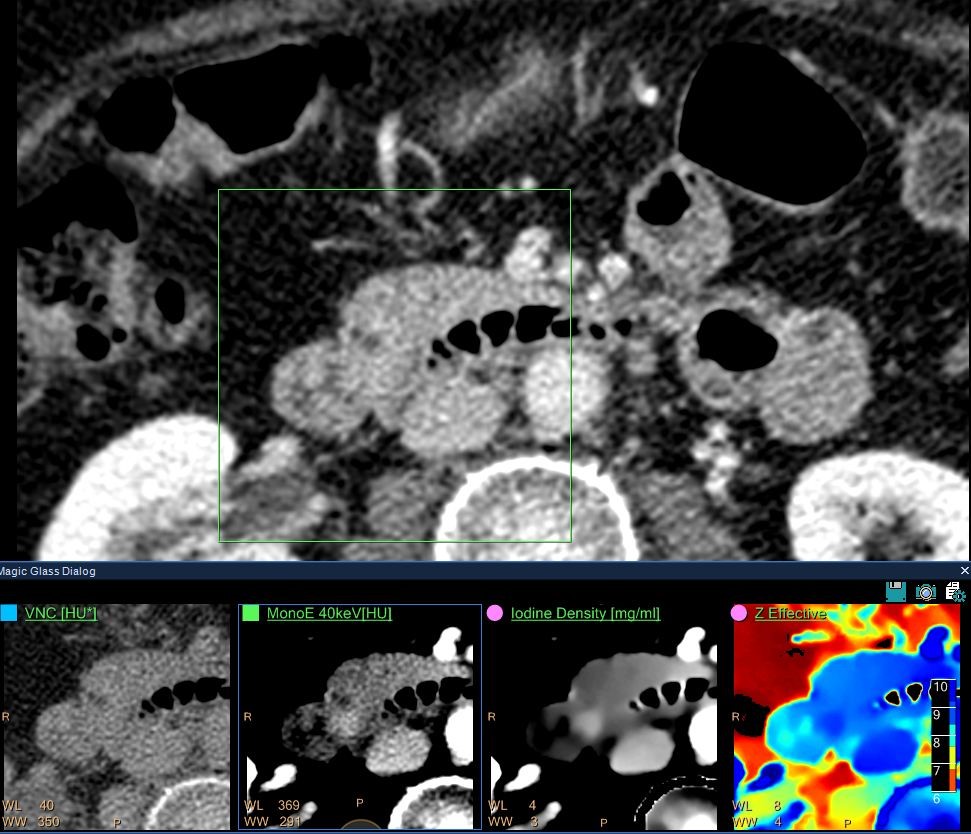

IQon Spectral CT consistently captures spectral information without special planning or set-up. In this case of a middle-aged female presenting to the ER complaining of abdominal pain, an abdomen/pelvis scan was ordered. The patient was scanned on the IQon Spectral CT.

Upon reviewing the conventional CT, the clinician noted that the pancreatic duct appeared to be dilated, but they could not identify the cause from the conventional images. The scan was immediately reviewed using Spectral Magic Glass, which allowed the radiologist to view five different spectral results without changing his workflow. Upon review of the various results, the clinician identified a lesion in the head of the pancreas and the patient was referred for an endoscopic ultrasound biopsy. That pathology report identified a tubular adenoma of the Ampulla of Vater.

Images courtesy of UCL Brussels, Belgium